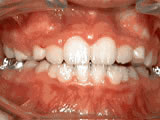

Open bite - Front teeth don't touch

Patient sucked her thumb as a young child. She started treatment at age 13. She had braces and a special appliance — called a crib — to retrain the tongue, for 28 months. Now she can bite the lettuce out of a sandwich.